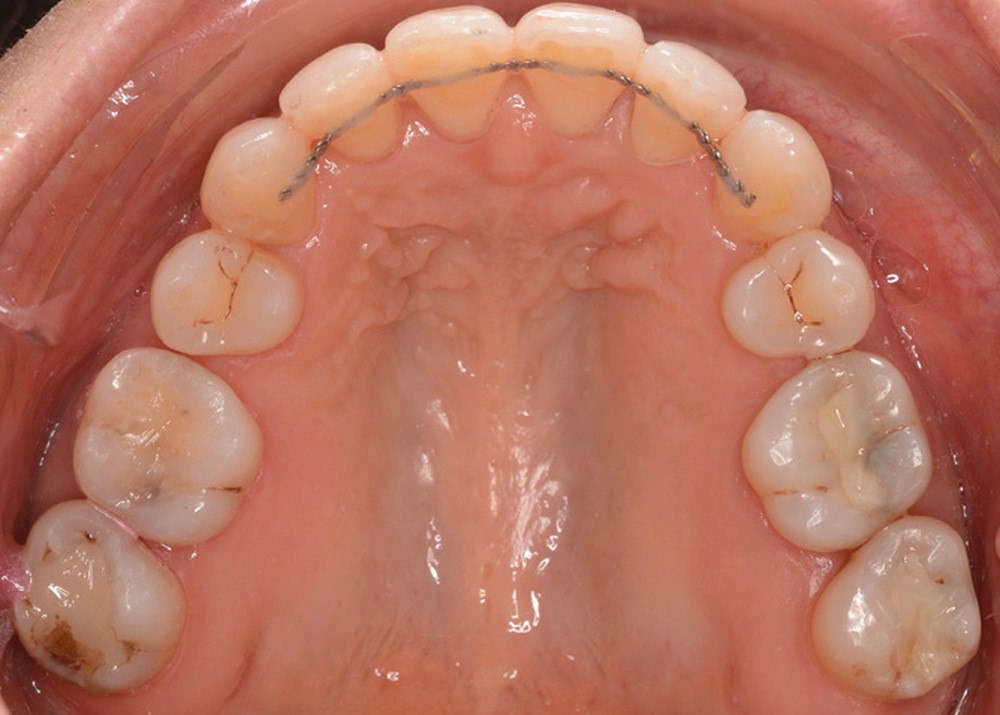

Un traitement en technique vestibulaire par appareillage multi-attaches .022 x .028 inch (prescription selon Roth) est entrepris, avec avulsion de prémolaires (15, 25, 34, 44).

La patiente ne supportant aucune cale occlusale, le collage de l’arcade mandibulaire est séquentiel afin de ne placer aucune attache en interférence occlusale. Le recul canin mandibulaire se fait grâce à des arcs sectionnels à boucle en Titane-Molybdène (TMA) .017 x .025 (fig. 10).

L’alignement et le nivellement maxillaires sont conduits en arc droit, et la mésialisation molaire réalisée en glissement, soutenue par des élastiques inter-arcades de classe III.

Le nivellement mandibulaire par ingresssion des incisives est mené via des arcs acier à la déformation avant de pouvoir recoller les brackets incisifs dans une position permettant de terminer le traitement en arc droit (fig. 11).